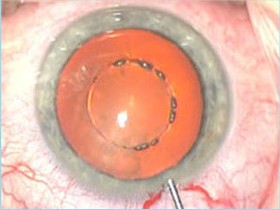

3、激光自动截囊

4、激光粉碎晶体核